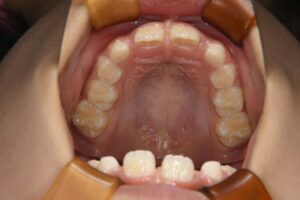

上唇をめくったときに 上の前歯のちょうど真ん中にあるすじのことです。

この状態のことを 〖上唇小帯高位付着〗といわれます。

上の前歯が生え変わる小学校低学年のころに小帯が長いままでいると、前歯の間に隙間ができる原因になることがあります。これを〖正中離開〗と呼び、前歯が通常よりも離れて生えてしまう、いわゆる『すきっぱ』になるという現象です。前歯の隙間は、前歯の隣の歯や後ろの歯の生える力によって隙間が狭くなることもありますが、長いままであると完全に隙間が閉じるということはなかなか難しくなります。